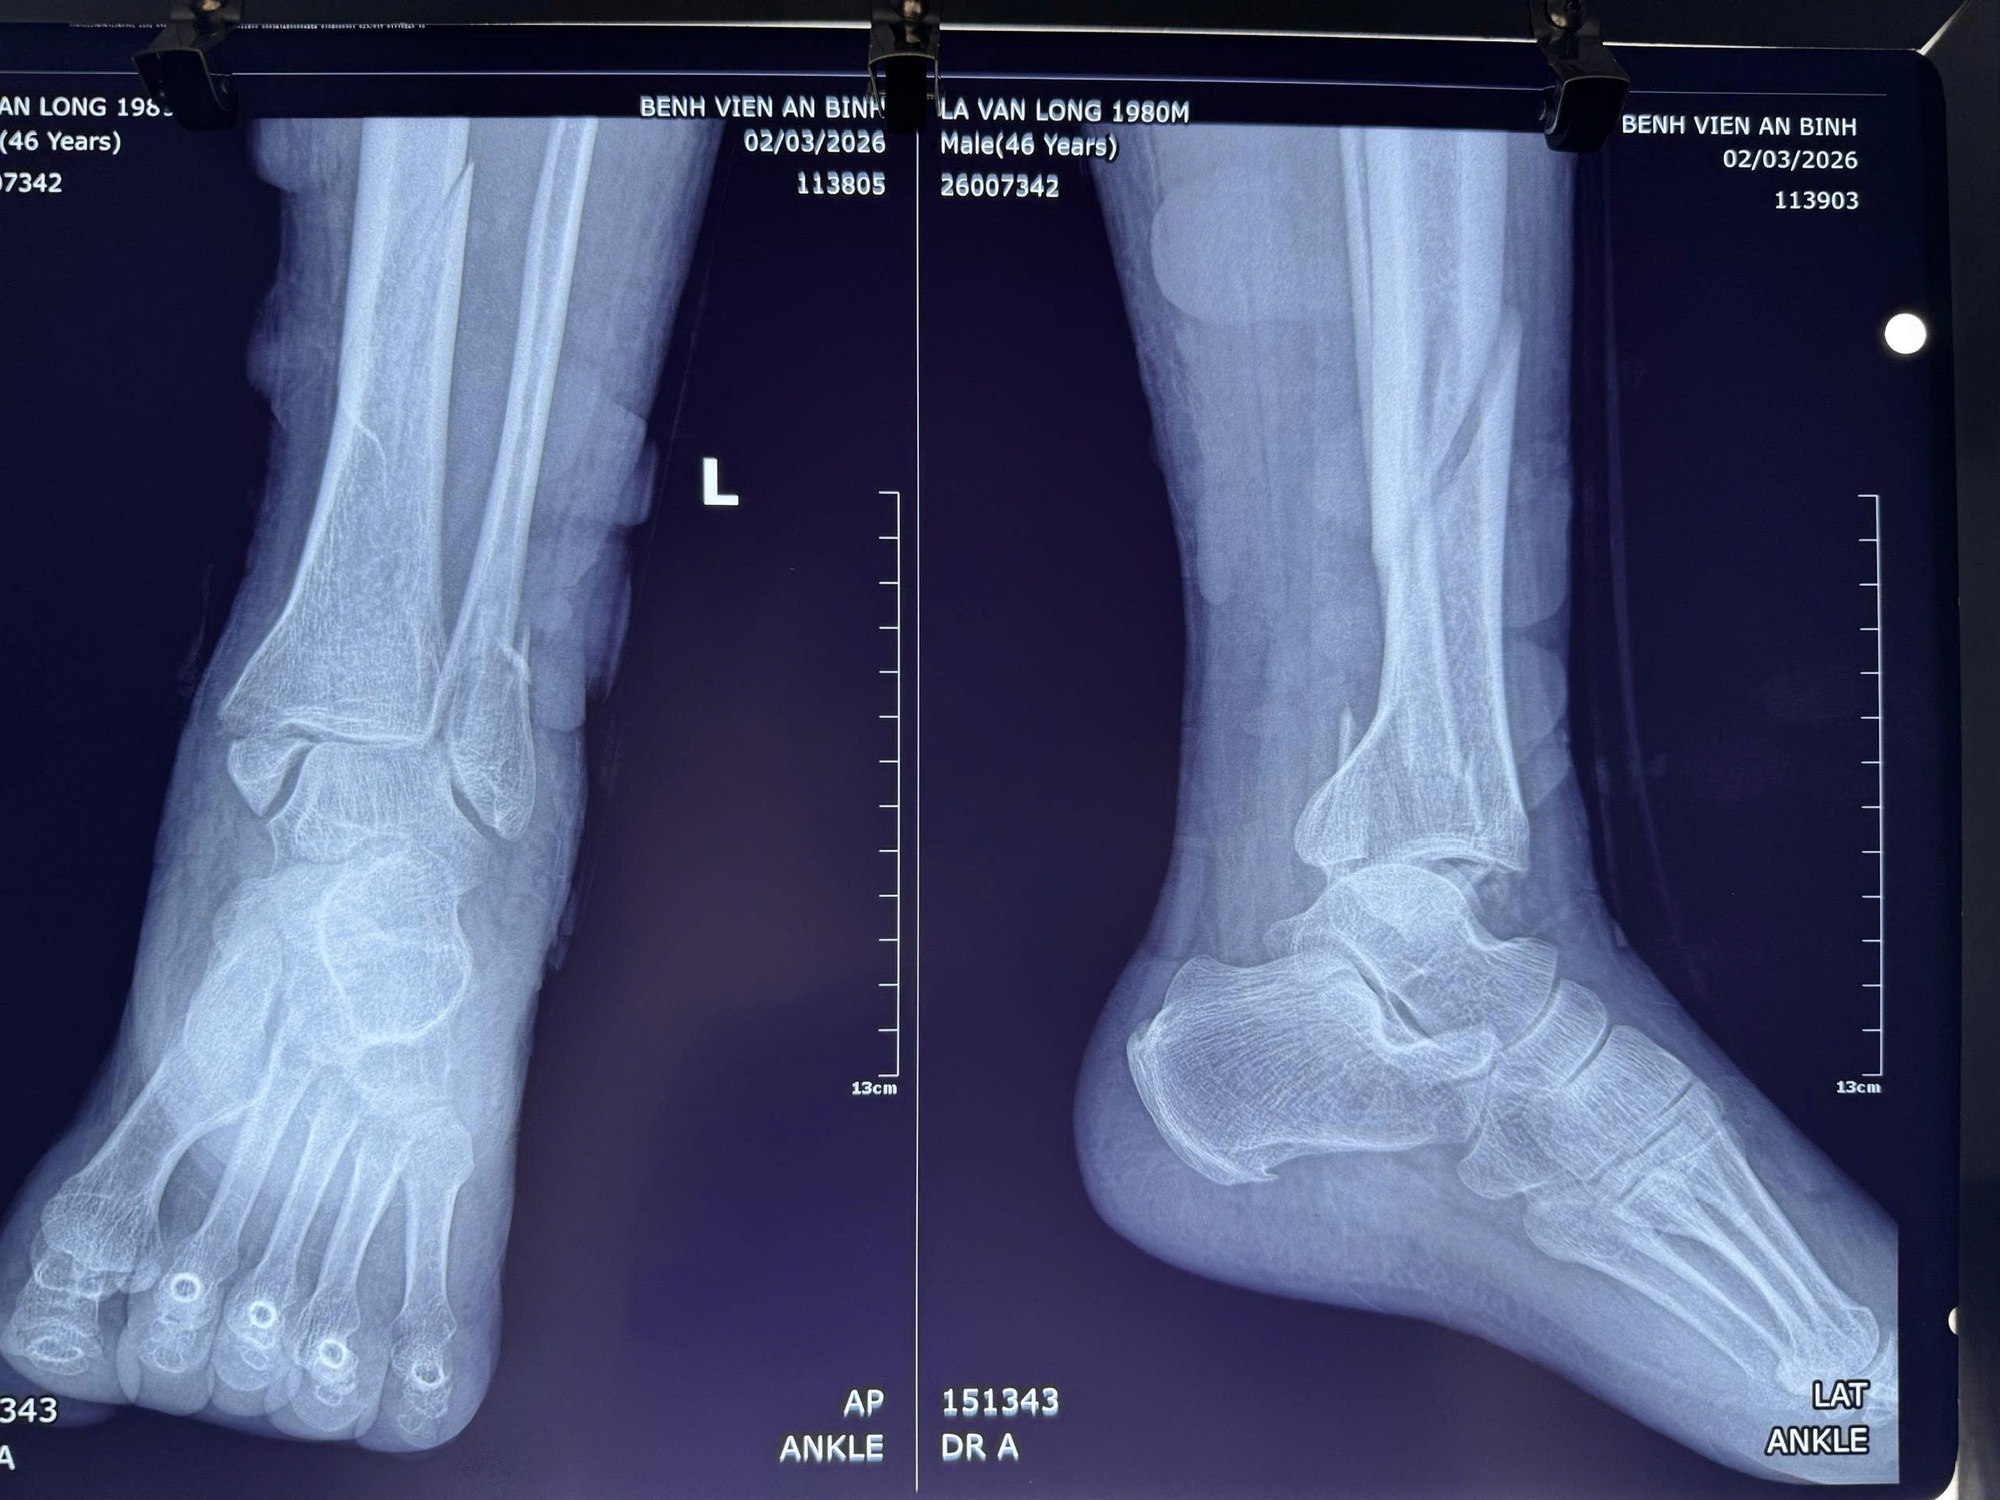

Những ngày đầu, bệnh nhân nghĩ rằng chỉ cần đắp thuốc vài hôm là khỏi. Nhưng chỉ sau 2 ngày, chân bắt đầu sưng to, nổi nhiều bọng nước, đau dữ dội và biến dạng cổ chân. Khi không thể chịu nổi cơn đau, bệnh nhân mới đến bệnh viện. Sau khi kiểm tra, bệnh nhân bị gãy phức tạp 3 mắt cá chân, gãy 1/3 dưới xương chày, bán trật khớp cổ chân, rối loạn dinh dưỡng mô mềm và viêm mô bào cẳng bàn chân trái.

Chụp X-quang cho thấy gãy phức tạp ba mắt cá, bán trật khớp cổ chân kèm gãy 1/3 dưới xương chày